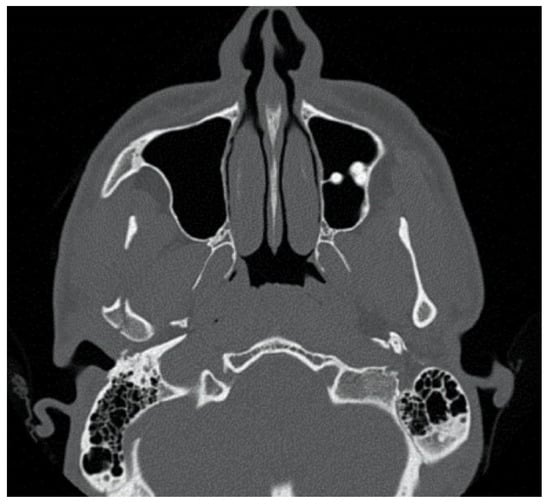

The second patient was a male, aged 20, with a right condylar diacapitular fracture (Figure 4). The patient also presented a coronal fracture of the element 43 due to the trauma. The other teeth were sound, but the 37 was unerupted. He presented a slight class III malocclusion and a posterior open bite on the left. In this case, there was the need to not exert force on the fractured tooth, and to balance the traction points of the rubber bands despite the absence of the 37, avoiding extrusive forces on the 27.

At the end of the IMF period, a control CT (computed tomography) scan was obtained for every patient.

Intracapsular fractures of the mandibular condyle are classified as type A—fractures through the medial condylar pole; type B—fractures through the lateral condylar pole with loss of vertical height of the mandibular ramus; or type M—multiple fragments, comminuted fractures. The majority of mandibular condyle fractures involve the condylar neck, with few reports of intracapsular fractures. Sagittal or vertical fractures of the mandibular condyle and chip fractures of the medial part of the condylar head are rarely found by conventional radiography and are more commonly detected by computed tomography (CT) scan [10].

Figure 4. Patient 2, male, aged 20, with a right condylar diacapitular fracture.